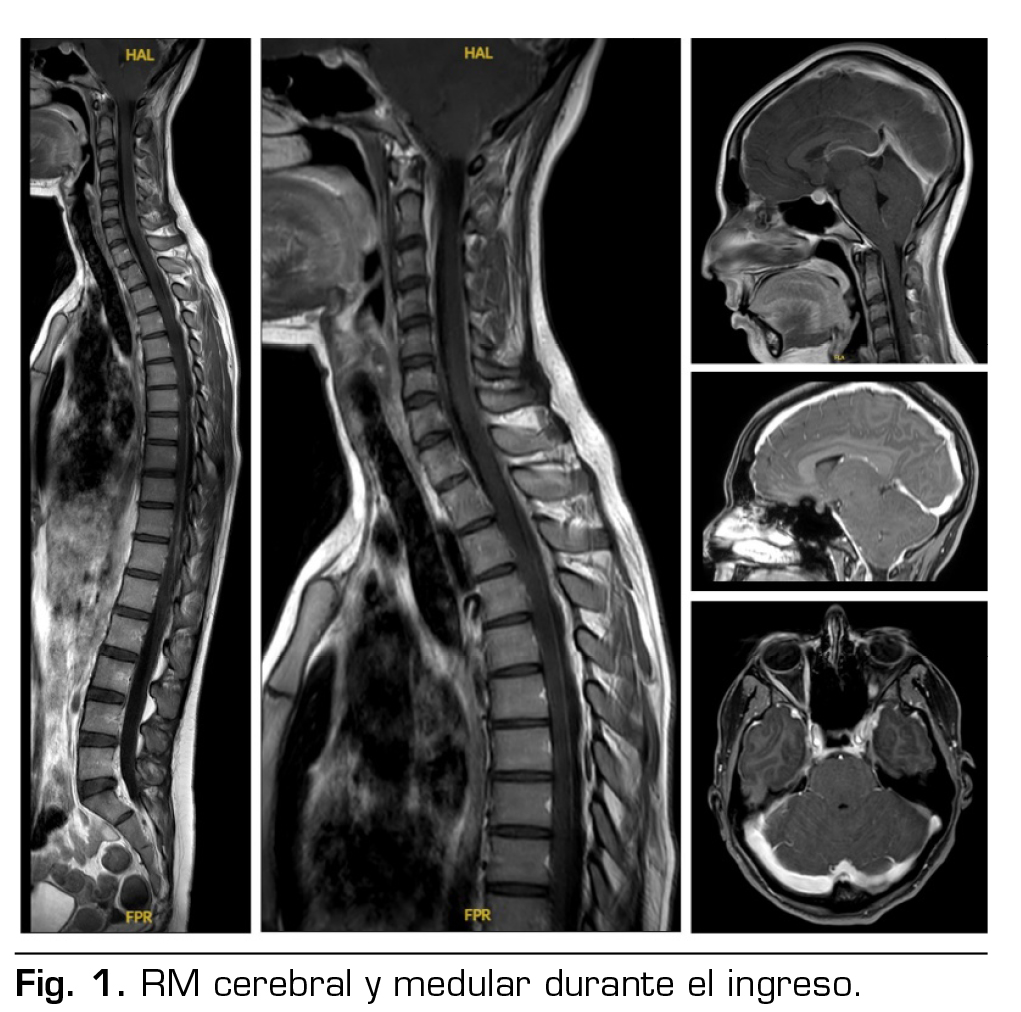

Pruebas complementarias: tomografía computarizada cerebral y analítica normales. RM cerebral y medular: signos de hipotensión intracraneal con engrosamiento dural y pequeñas colecciones laminares en convexidad frontoparietal, colecciones probablemente epidurales en la porción anterior cervical baja y en la región posterior a nivel dorsolumbar (Figura 1).

No se había podido demostrar la existencia de fuga de LCR, pero la presencia de una colección líquida de 57 mm de longitud por delante de la columna anterior del LCR en los segmentos C6-T2, una colección epidural posterior desde T1 hasta T7, y las colecciones en la convexidad frontoparietal, sugerían la localización de las probables fugas, y decidimos realizar un parche hemático no dirigido.